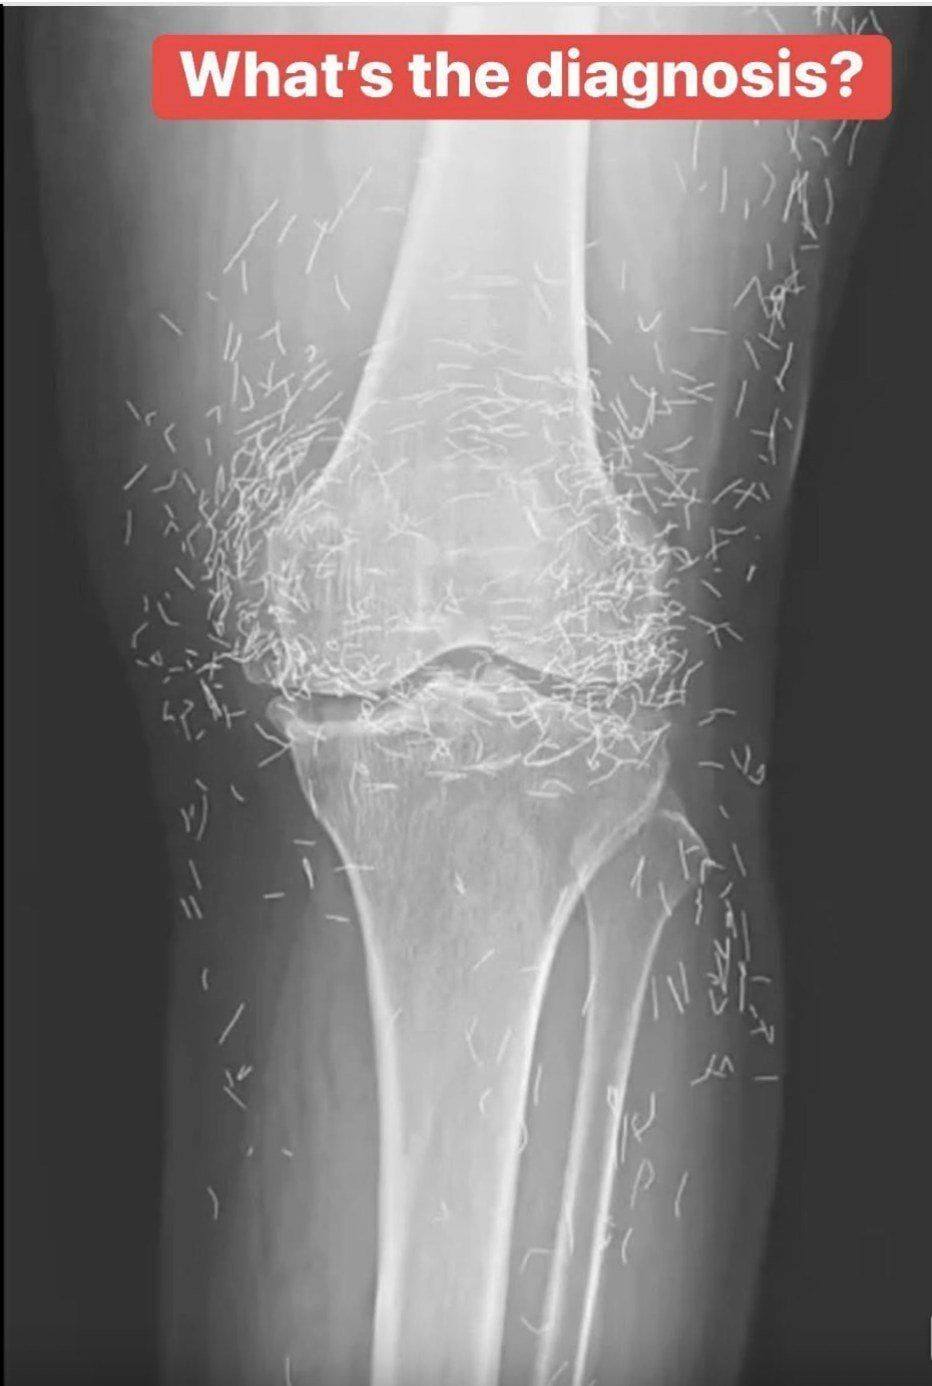

Years later, when doctors took X-rays to evaluate her knee condition, they weren’t prepared for what appeared on the images. Her knees were filled with dozens of bright, metallic flecks — tiny needles embedded deep within the joint area.

The findings were later documented in a case published by the New England Journal of Medicine.

Beyond inflammation, the needles created another problem: imaging complications. Metal objects can obscure parts of the anatomy on X-rays, making it harder for doctors to clearly assess joint damage or disease progression.